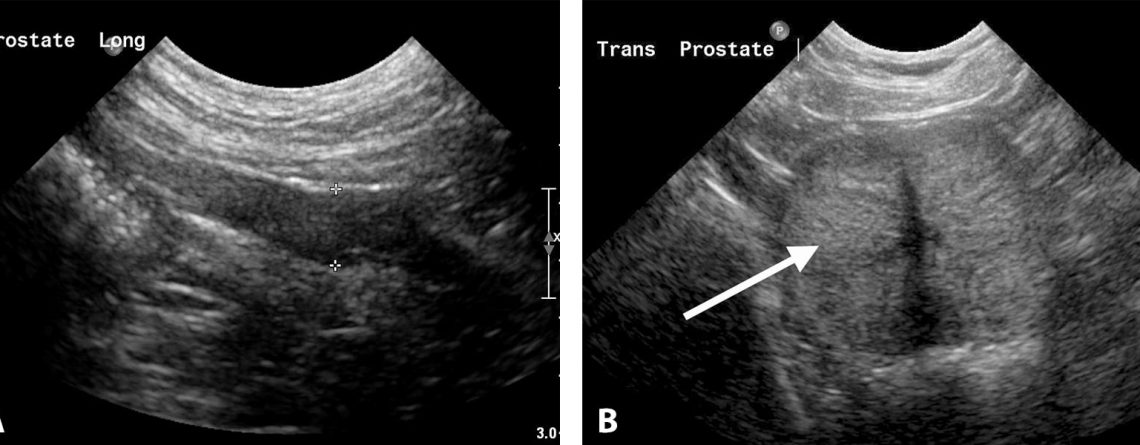

Prostat Hastalıklarının Ultrasonografik Muayenesi

Erkek üreme organlarından bir olan prostatın ultrasonografik olarak muayenesi; köpeklerde kedilerden daha sık olarak yapılmaktadır. Köpeklerdeki tek erkek aksesuar bez olan prostat bezi; seminal plazma...